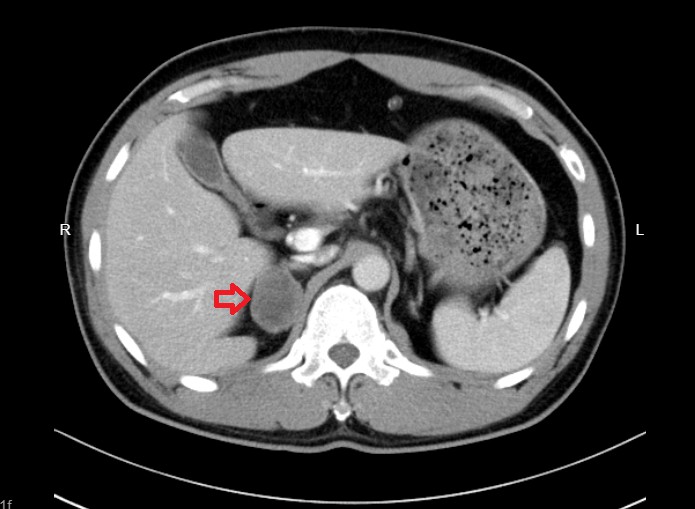

案例二